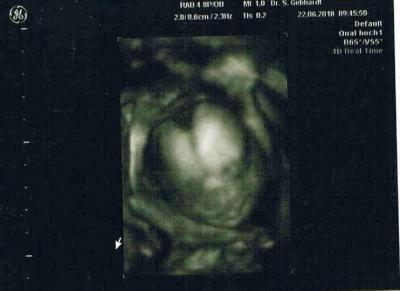

hallo, war heute beim us, erst sah alles gut aus,und sie ist sich sehr sicher das es ein mädchen wird!!!!! vorhin rief sie an und sagte das die leukozyten viel zu hoch sind und das es auf eine infektion der gebärmutter hindeuten könnte! nun muss ich donnerstag nochmal hin blut abnehmen nochmal. hoffe das mein zahn schuld ist der seit tagen schmerzt!!!!!!!!!!! war schon beim zahndoc grad! drückt mir die daumen das donnerstag der wert etwas runter ist bitte!!!!!!

Bild zu hallo us bild - Forum für November - Mamis